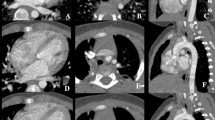

Patient background information is described in Table 1. A total of 221 patients (71.1 ± 12.4 years, 174 males) were included. Representative vascular dynamic CT images are shown in Fig. 3.

Representative CT image of a 61-year-old female patient who was administered with an iodine contrast agent (iopamidol, 370 mgI/mL) from the right antecubital vein. Both lung volumes in the a unenhanced, b arterial phase, and c delayed phase images were 2144, 1739, and 2434 mL, respectively. The tracheal diameters at the thoracic inlet in the unenhanced, arterial phase, and delayed phase were 13.6, 12.6, and 14.3 mm, respectively